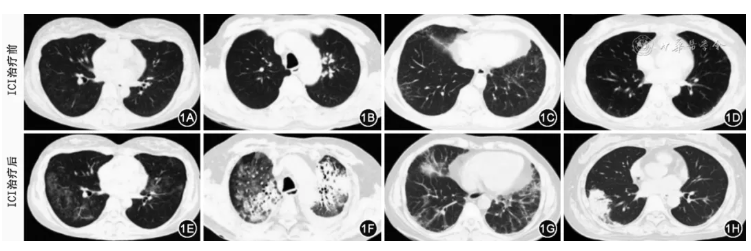

CIP是药物相关间质性肺炎,胸部影像学中的胸部CT是诊断CIP必要的关键的检查,也是评价CIP严重程度和评价预后的重要客观方法。与其他间质性肺疾病(ILD)类似,胸部高分辨率CT(HRCT)能更好地评价CIP的形态学特征。常规推荐胸部HRCT作为CIP诊断评价的首要检查。CIP患者的胸部CT影像学表现多样(图1),主要包括机化性肺炎样改变、非特异性间质性肺炎样改变、过敏性肺炎样改变、弥漫性肺泡损伤(急性间质性肺炎或急性呼吸窘迫综合征)样改变和普通型间质性肺炎样改变等[2,38]。此外,肺炎的影像学类型可能与临床严重程度和分级相关,如弥漫性肺泡损伤(急性间质性肺炎或急性呼吸窘迫综合征)样改变提示较高级别的肺炎以及较差的临床预后,其次是机化性肺炎样改变,而非特异性间质性肺炎样改变和过敏性肺炎样改变与较低级别的肺炎相关[12,39, 40]。胸部CT还可表现为其他免疫相关肺损伤模式,包括胸膜病变(胸膜增厚、胸腔积液或多浆膜腔积液),肺结节病样肉芽肿性反应和胸内淋巴结肿大等[41, 42]。一般不推荐常规开展造影剂增强检查,但若疑诊并发肺栓塞时,建议尽早行CT肺动脉造影(CTPA)联合 CT静脉造影(CTV)检查。PET-CT在CIP的诊断和随访中的作用尚不清楚,因为PET-CT对于CIP、恶性肿瘤以及感染的鉴别诊断缺乏特异性,因此不常规推荐PET-CT作为CIP诊断评价的手段。

图1 免疫检查点抑制剂(ICI)相关间质性肺炎常见影像学表现,其中图1A、1E为非特异性间质性肺炎型,图1B、1F为弥漫性肺损伤型,图1C、1G为非特异性肺炎合并机化性肺炎,图1D、1H为机化性肺炎型